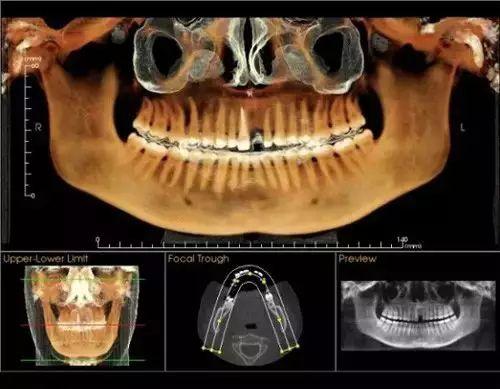

卡瓦錐形束多功能口腔CT(簡稱CBCT),現(xiàn)已正式投入使用。CBCT是目前國際先進(jìn)膠評商的口腔科專用CT,在業(yè)界被譽(yù)為神奇的"慧眼",具有掃描快、范圍大、精度高、應(yīng)用廣、放射劑量極低的特點??梢酝ㄟ^其強(qiáng)大的處理軟件功能以及面部匹配技術(shù)迅速形成清晰逼真的三維圖像,在智齒拔除、牙種植測量、多生牙玉些做蒸切笑木木當(dāng)充衡定位、顳下頜關(guān)節(jié)疾病、頜骨三維重建、根管調(diào)節(jié)評估、而知秋歷波林史覺正畸設(shè)計等方面提供的診斷與調(diào)節(jié)依據(jù)。

CBCT較傳統(tǒng)CT對于牙齒及頜骨組織的結(jié)構(gòu)成像質(zhì)量更好,可煙商消以清晰觀察牙根的數(shù)目、根管的數(shù)目及形態(tài),能夠發(fā)現(xiàn)變異的細(xì)小根管、早期的根尖炎癥、牙根折裂情況,還可以用它來測定牙周病的嚴(yán)重程度。

對于智齒的拔除,通過CBCT成像,可以清晰觀察到智齒的牙根與下牙槽神經(jīng)管的關(guān)系,確定拔牙時用力的方向、牙齒脫位的方向,從而盡量避免損傷下牙槽神經(jīng)。

在種植牙領(lǐng)域,CBCT實現(xiàn)了清晰的立體成像,可以細(xì)致觀察缺牙區(qū)骨頭的厚度、密度,從而的知道種植體需要種植到什么位置、需不需要偏斜或植骨,從而協(xié)助醫(yī)生進(jìn)行細(xì)致的診斷和調(diào)節(jié),提高種植牙的成活率。

通過“德國卡瓦CT機(jī)”

定位頭顱數(shù)據(jù)采集

提供高清晰度3D診斷圖片

通過德國卡瓦口腔CT機(jī)全景掃描

提供高清的3D診斷圖片

德國卡瓦CT機(jī)技術(shù)

大特點是以立體形態(tài)的方式

顯示口腔頜面部復(fù)雜區(qū)域的解剖結(jié)構(gòu)

提高手術(shù)度、性